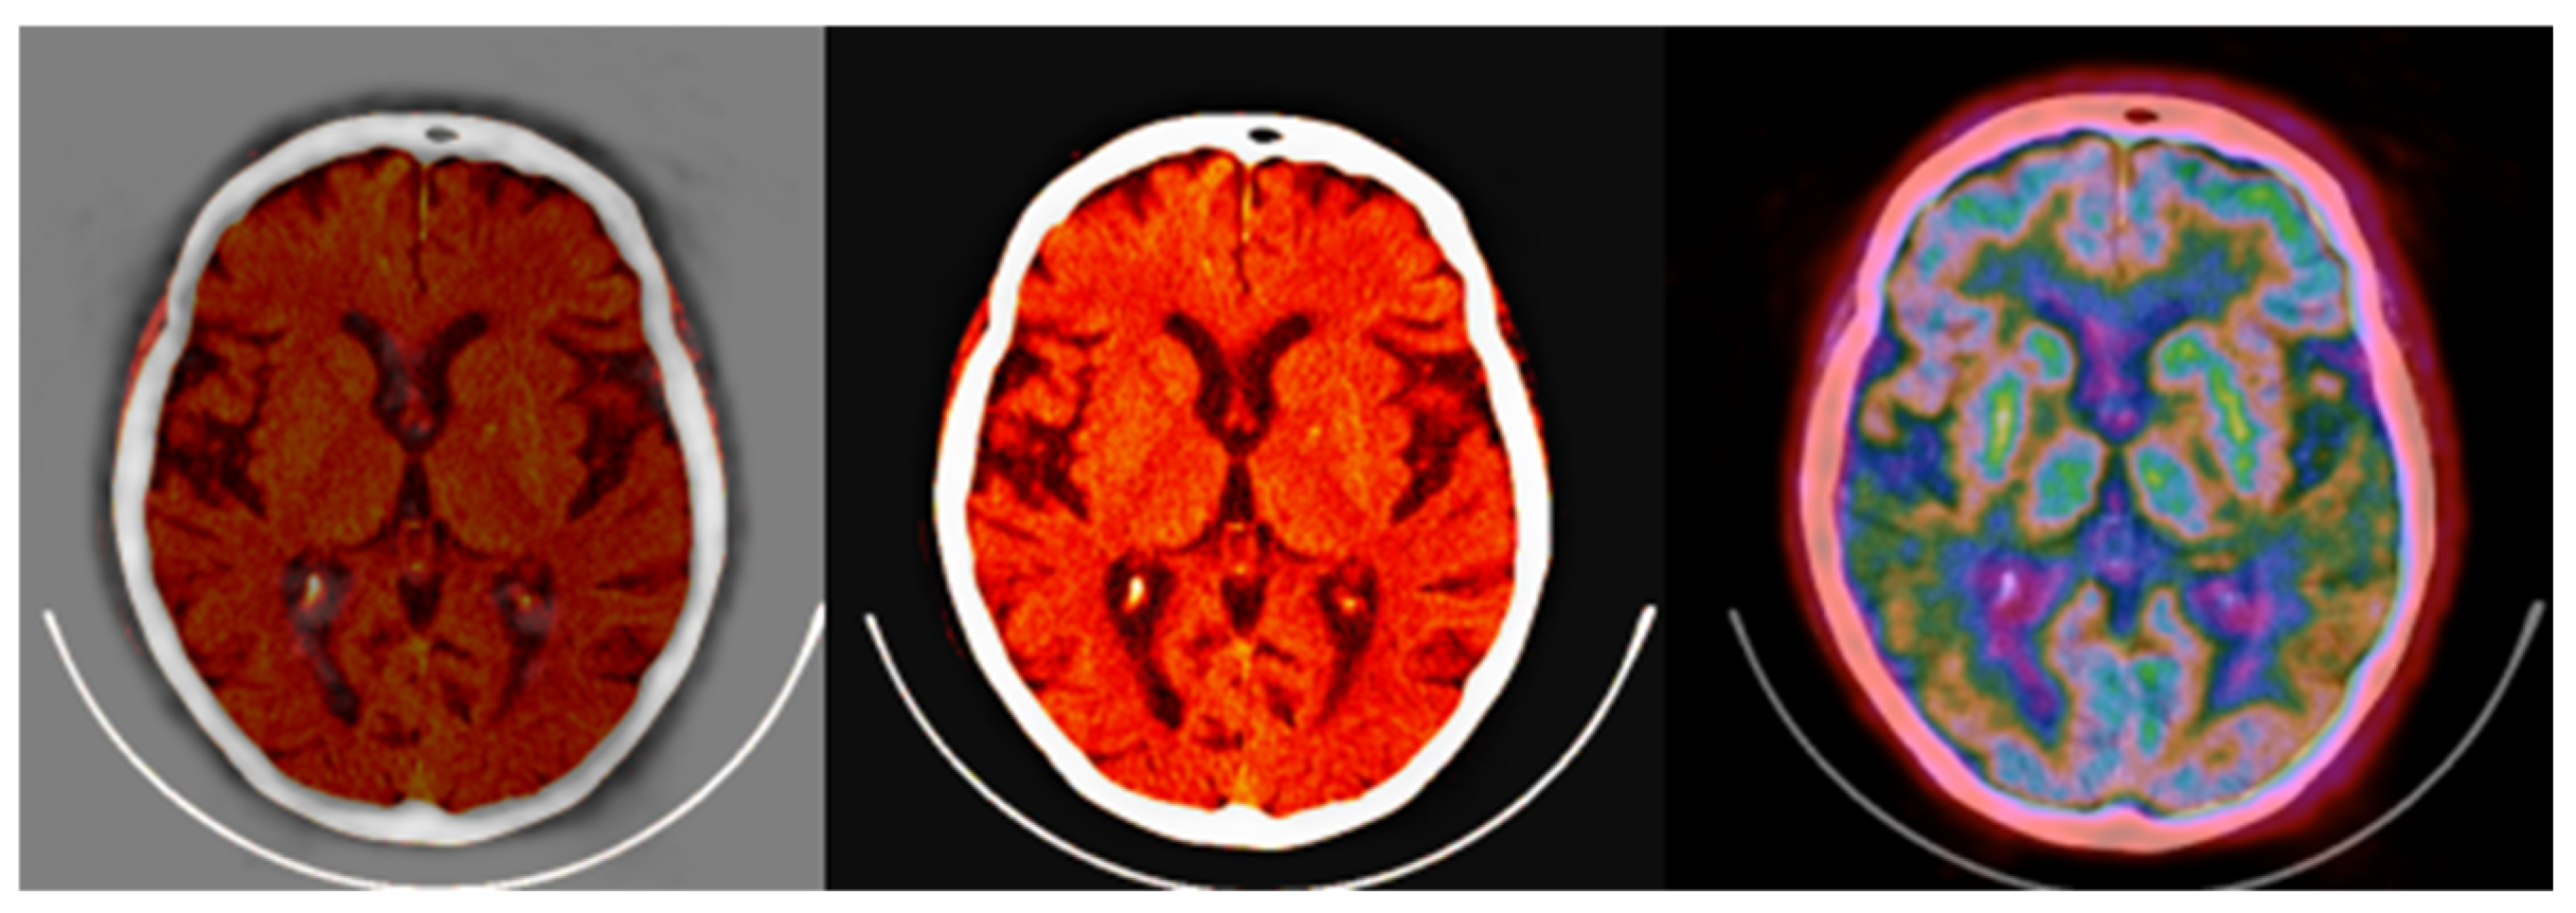

Figure 14.

Standard brain CT grayscale image (left), Colormap Folding applied to the corresponding PET image with 3 folds (middle) and fused scale-adjusted PET image with 50% of the CT image (right).

The fused images obtained with the proposed colormap folding may be compared with standard PET/CT fused data available on all manufacturers’ clinical workstation–user interfaces. Figure 15 presents typical results obtained for our data from a standard clinical interface and compares them to the fused image in Figure 14.

Figure 15.

(left,middle) images were obtained from a verified and clinically used PET/CT DICOM viewer software and represent the classical PET/CT fusion that may be used in clinical practice. These results may be compared with the 3-fold PET/CT fusion of Figure 14 using the proposed methodology.